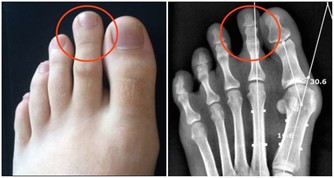

三、肢體麻木

許多血栓患者在開始時表現出不同程度的麻木感。你可能會以為是壓到了或者是累著了,直到發展為疼痛才會想到就醫。但其實這可能是由於心臟或者其他部位的血栓進入了你的動脈。

腿動脈栓塞以後,這部分腿部就會缺血,變得皮膚蒼白、溫度降低,甚至連足背動脈都可能摸不到了。